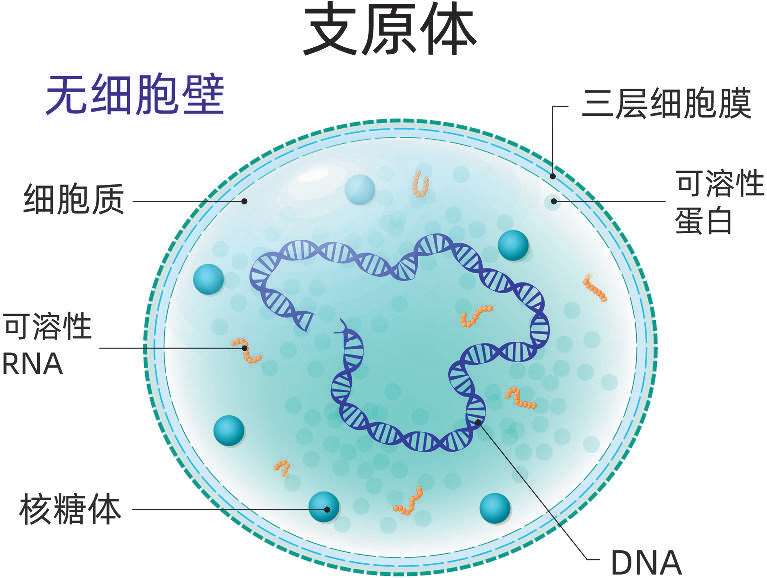

支原体(mycoplasma)是一类没有细胞壁的原核生物,是目前发现的最小的原核生物。与人类疾病关系密切的支原体是肺炎支原体,结构简单,多数呈球形,没有细胞壁,只有三层结构的细胞膜,细胞柔软,具多形性。

肺炎支原体是引起支原体肺炎的病原体。支原体肺炎是我国5岁及以上儿童最主要的社区获得性肺炎。

·临床表现差异较大。

·支原体感染,轻者可不发病,或仅表现为上呼吸道感染,重者可导致支原体肺炎。

·起病时有剧烈、阵发性的刺激性干咳,可伴有发热、头痛、流涕、咽痛等,大部分预后良好。